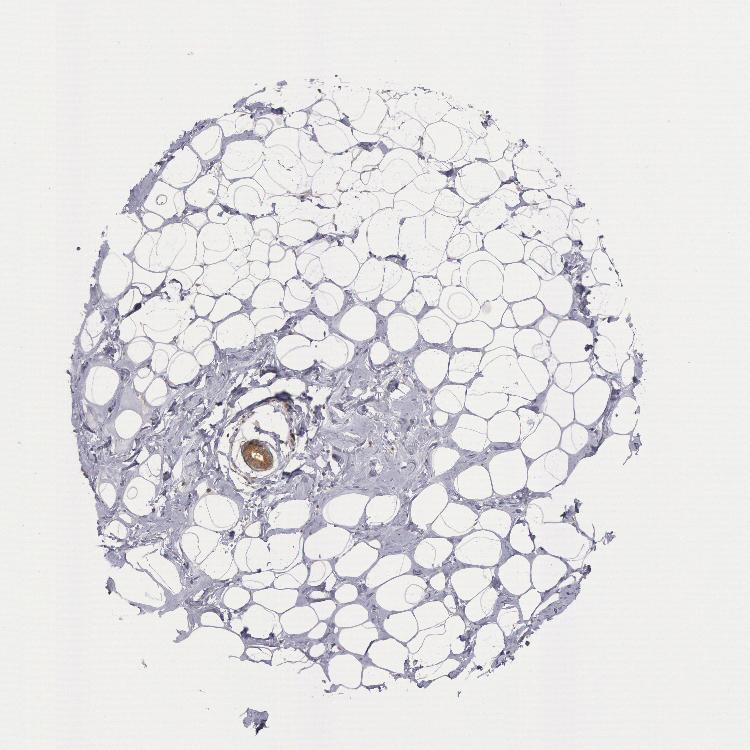

BREAST - Antibody stainingi

Antibody staining in the annotated cell types in the current human tissue is reported as not detected, low, medium, or high, based on conventional immunohistochemistry profiling in selected tissues. This score is based on the combination of the staining intensity and fraction of stained cells.

Each image is clickable and will lead to virtual microscopy that enables deeper exploration of all samples and also displays staining intensity scores, fraction scores and subcellular localization as well as patient and tissue information for each sample.

Antibody HPA001328Antibody HPA071048Antibody CAB004552Antibody CAB080447Antibody CAB080451Antibody CAB080531

Adipocytes Not detectedNot detectedNot detected-Not detectedHigh

Glandular cells MediumMediumHighMediumMediumHigh

Myoepithelial cells LowNot detectedMediumNot detectedMediumHigh